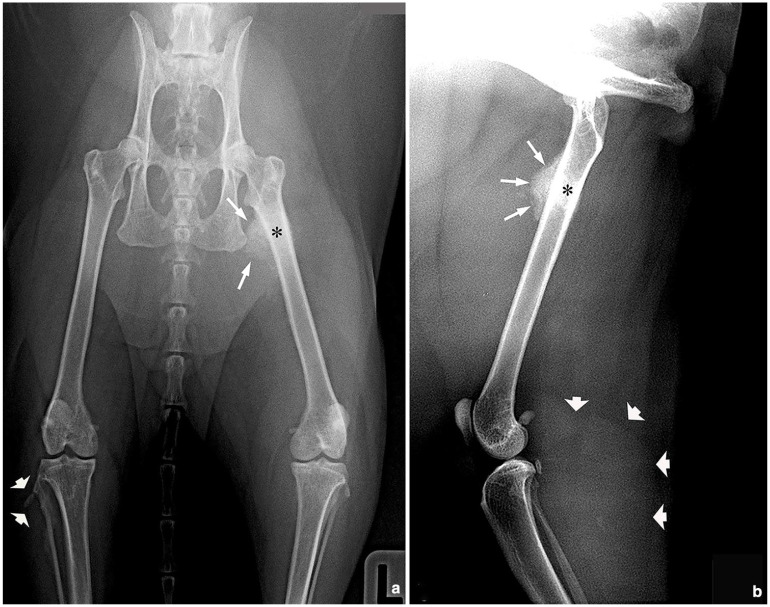

Case summary: A 13-year-old male castrated domestic shorthair cat presented with a 2-month history of progressive lameness, poor appetite and constipation. Physical examination revealed palpable lesions in muscles of several extremities. Ultrasound examination confirmed the presence of round lesions with a hypo- or anechoic centre within the muscles. These lesions were characterised by an anechoic, occasionally trabeculated, central area surrounded by a hyperechoic band with heterogeneous echotexture. In total, seven lesions affecting six appendicular muscles were detected in different evolution stages, as suggested by their sizes and ultrasonographic features. Fine-needle aspiration of the muscle lesions revealed nests and isolated pleomorphic large neoplastic cells consistent with a carcinoma (vs sarcoma) and one mass was surgically removed. The histological and immunohistochemical studies confirmed a diagnosis of metastatic urothelial carcinoma. Although this neoplasia typically originates from the urothelium of the urinary bladder or renal pelvis, the primary tumour could not be detected in repeated abdominal ultrasound examinations. The cat was euthanased and further evaluations were declined by the author.

Relevance and novel information: Urothelial carcinoma is a rare and highly aggressive neoplasia in the cat. While metastasis to regional lymph nodes and lungs are common in cats and dogs, to the authors' knowledge, there have been no reports of metastasis to multiple appendicular muscles in cats. This clinical presentation should be considered in the differential diagnoses of multiple nodular or cystic lesions affecting long muscles in cats.